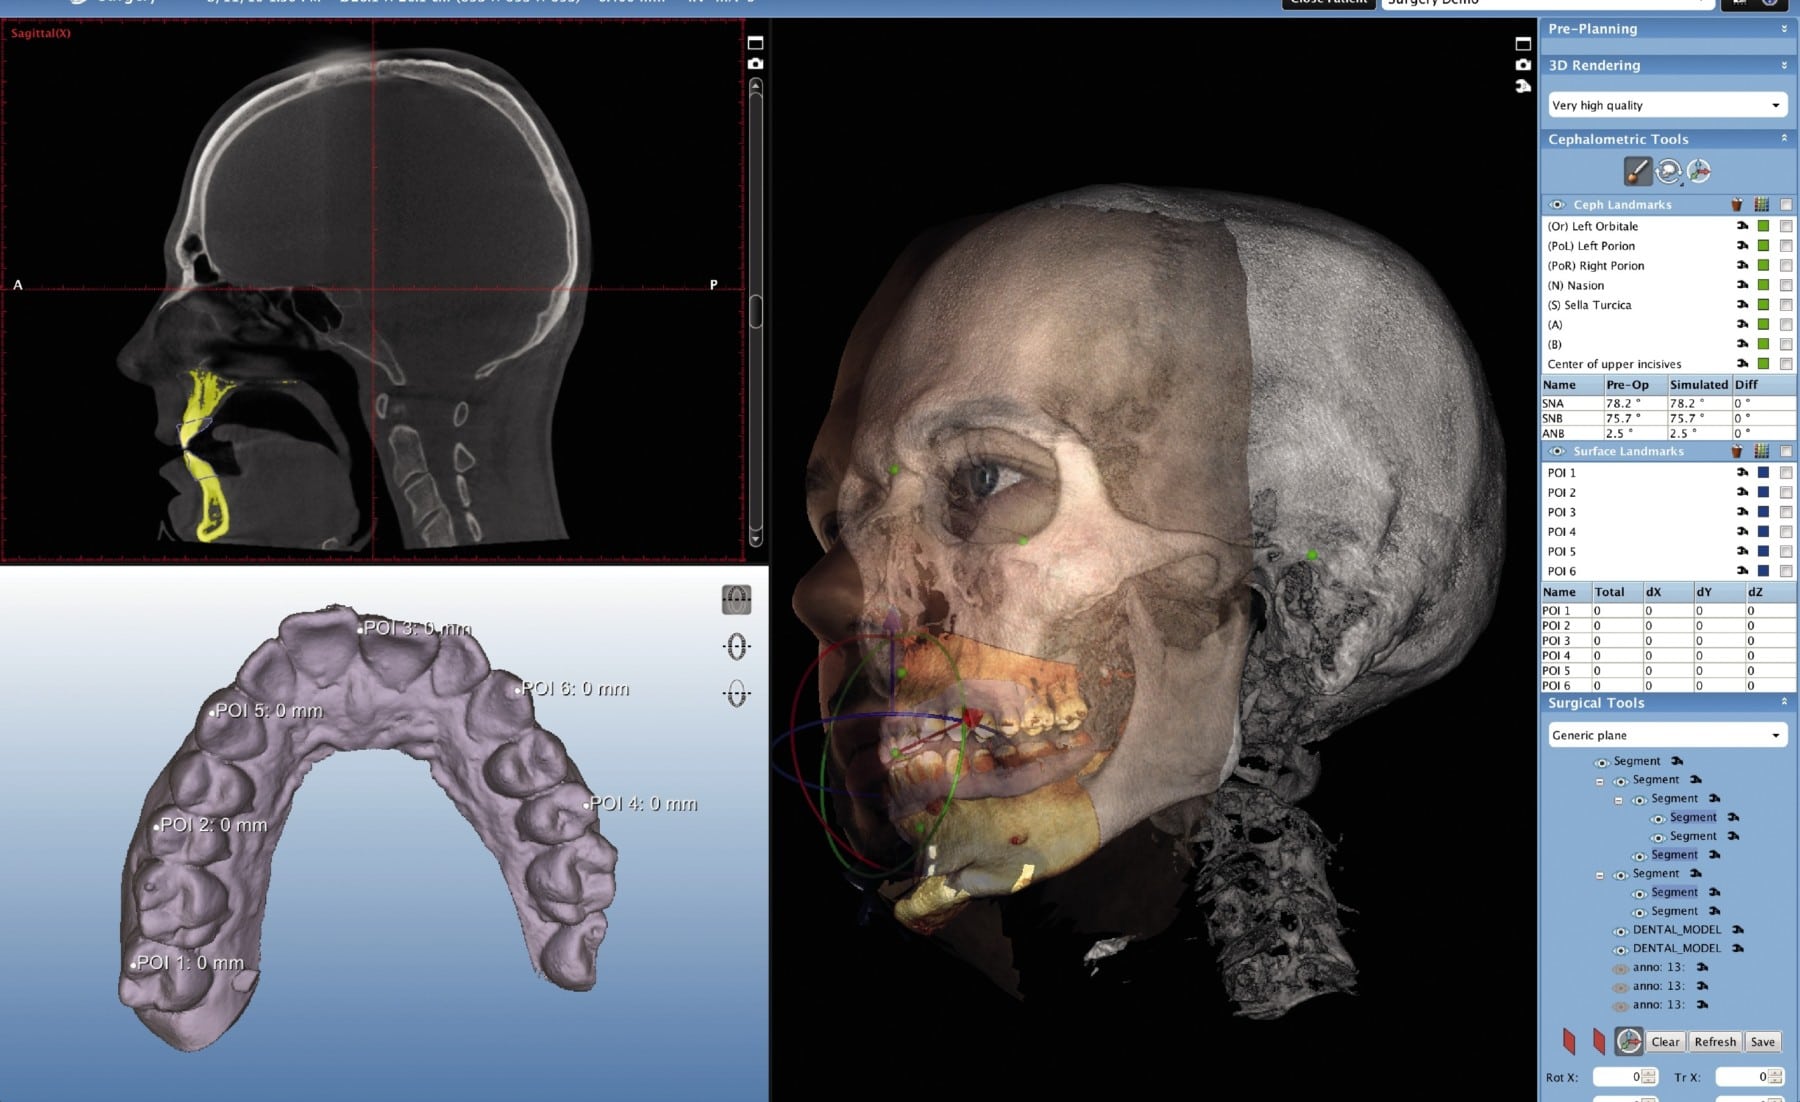

CBCT scan pricing in 2026 is no longer solely dictated by hardware acquisition cost. The convergence of photon-counting detector (PCD) technology, AI-driven iterative reconstruction, and cloud-native workflow integration has decoupled scan cost from traditional hardware depreciation models. Current pricing structures reflect operational efficiency gains of 32-47% over 2023 benchmarks, with clinical accuracy now quantifiably tied to reconstruction algorithms rather than voxel size alone.

Engineering Principle: Hybrid reconstruction pipelines now integrate model-based IR (MBIR) with convolutional neural networks (CNNs). The CNN (typically a 3D U-Net variant) pre-processes sinogram data to suppress quantum noise, while MBIR enforces physical constraints (Poisson statistics, system geometry). Training leverages synthetic datasets generated via Monte Carlo simulation (Geant4) validated against NIST-traceable phantoms.

Engineering Principle: Co-axial blue LED structured light projectors (1920×1080 DMD) capture intraoral surface geometry during CBCT acquisition. Phase-shifting algorithms register optical data to volumetric data via mutual information maximization, correcting for patient motion artifacts at sub-voxel resolution (0.03mm RMS).

| Metal Artifact Index (MAI) | 0.38 ± 0.12 | 0.19 ± 0.07 | PCD energy-bin decomposition + CNN metal trace inpainting | 92% reduction in manual artifact correction time |

| Geometric Distortion (ISO 15725) | 0.28 mm | 0.11 mm | Real-time gantry flex compensation via FEM modeling | Eliminates need for physical calibration phantoms |

| Scan-to-CAD Time | 47.3 min | 12.1 min | Automated segmentation (nnU-Net v4) + optical-CBCT fusion | 3.9x lab throughput increase |

| CBCT-Reference Model Deviation | 82.3 μm | 34.7 μm | Sub-voxel surface registration via structured light | Margin acceptance rate: 98.7% vs 89.2% |

For Labs: Prioritize systems with open reconstruction SDKs (e.g., OSIRIX MD, 3D Slicer plugins). Closed “black box” AI reconstruction impedes validation against lab-specific materials (zirconia, PEEK). Demand access to raw sinogram data for artifact troubleshooting.

For Clinics: Verify DICOM Supplement 224 compliance for structured light data embedding. Systems storing optical data as private DICOM tags create interoperability failures with third-party CAD platforms. Audit AI reconstruction validation using ACR CT phantom protocols.